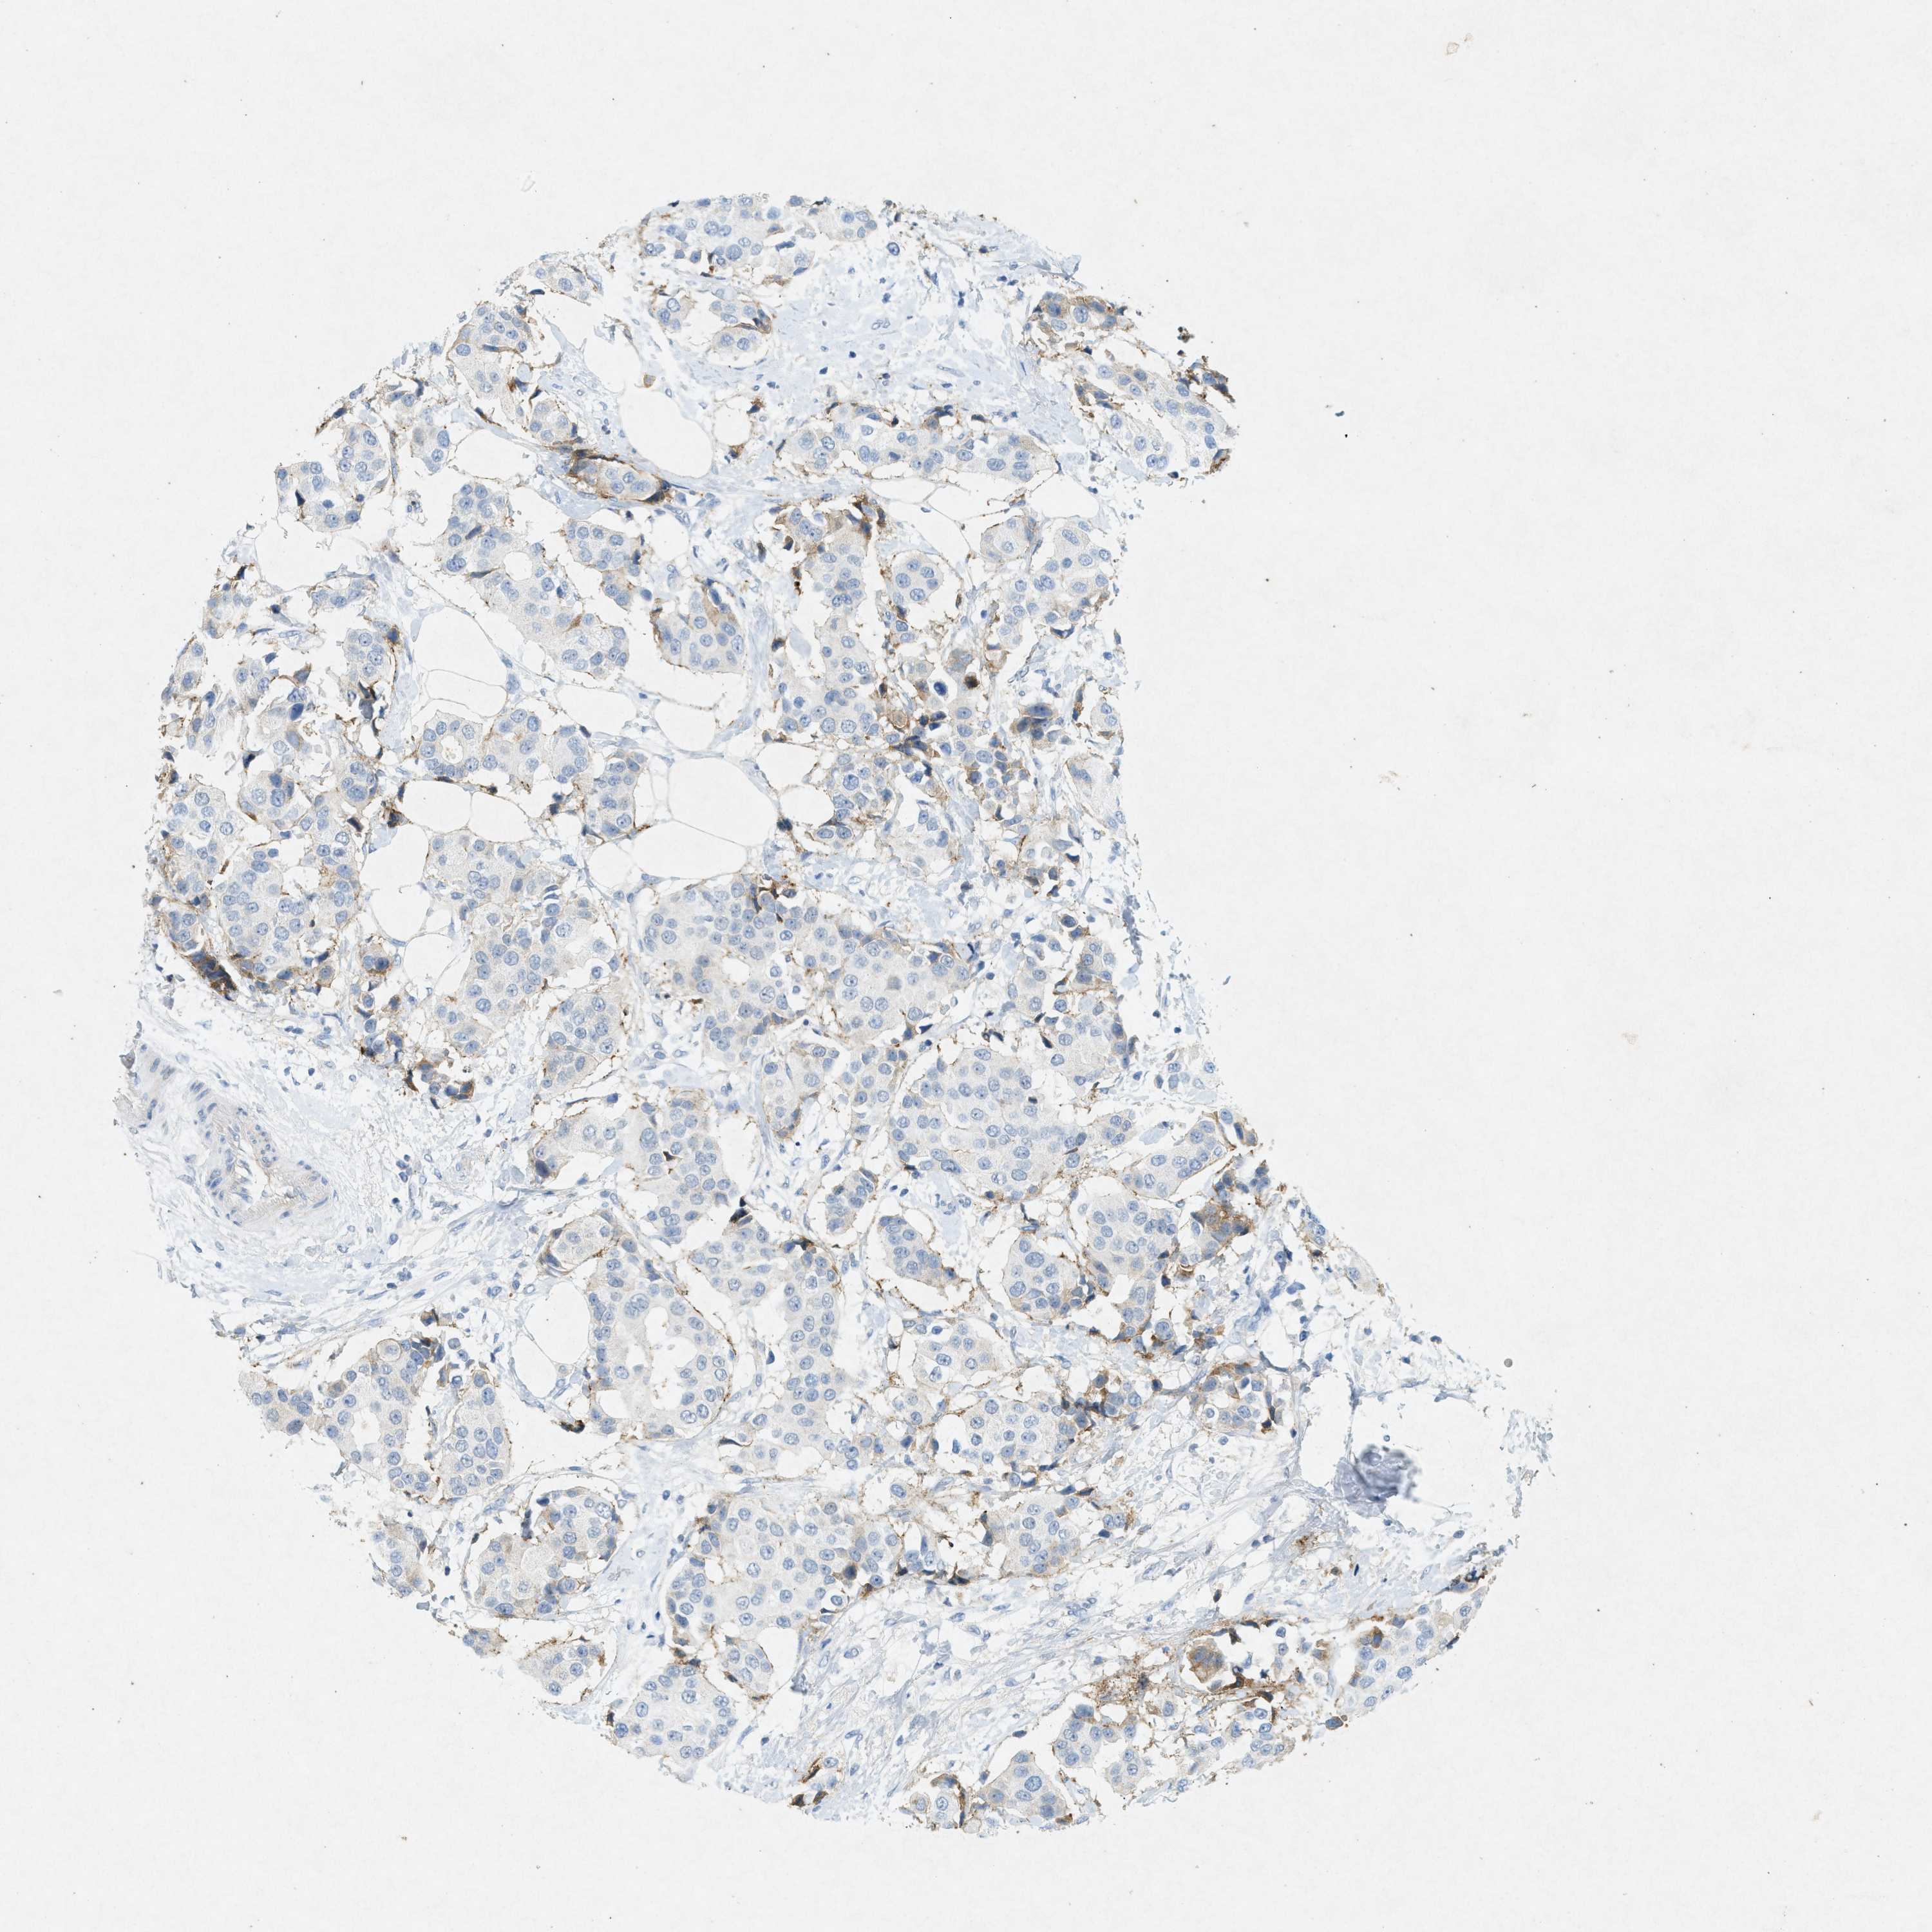

CANCER BREAST CANCER Show tissue menu

BRCA TCGA BRCA VALIDATION PROTEIN EXPRESSION